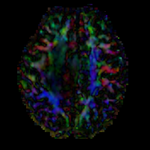

this is the fixed T2 reference image. All images are aligned into this space this is the fixed T2 reference image. All images are aligned into this space lleft this is the DTI Baseline scan, to be registered with the T2 this is the DTI tensor image, in the same orientation as the DTI Baseline

moving image 2b

DTI tensor

• moving: Tensor data of DTI volume, oblique, same orientation as Baseline image. The result Xform will be applied to this volume. The original DWI has 64 directions, the extracted DTI volume has 9 scalars, i.e. 128 x 128 x 40 x 9